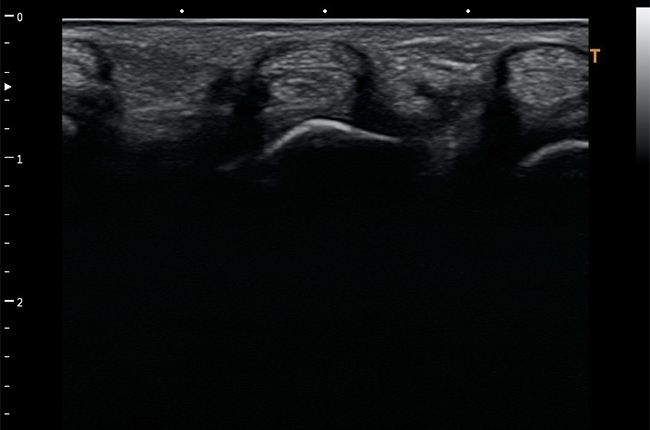

Поверхневі органи та малі структури

Скелетно-м'язова система